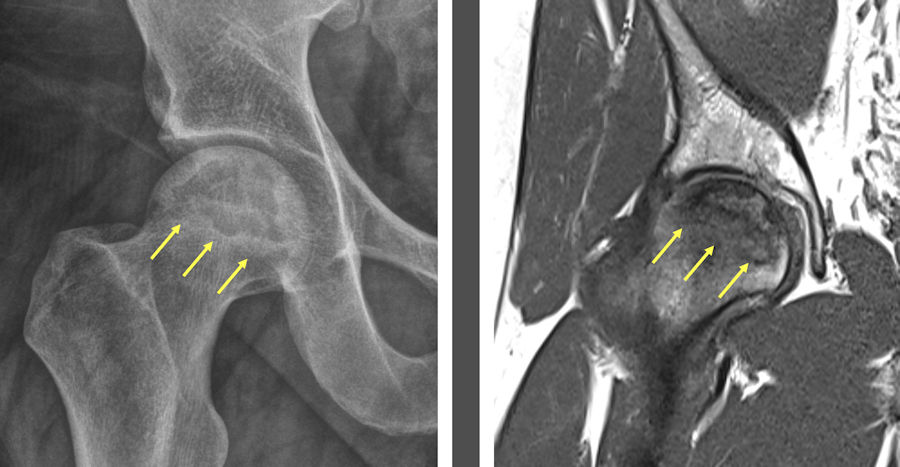

Femur başı avasküler nekrozunda kalça eklemi koruyucu cerrahiler

Femur Başı Avasküler nekrozu, kalça eklemini oluşturan kemiklerden birisi olan femur başının beslenme bozukluğuna bağlı gelişen ve uygun tedavi edilmezse eklemde geri dönüşü olmayan hasara yol açan bir hastalıktır. Femur başına giden damarların yaralanması veya tıkanması ile başlayan olaylar zinciri, çoğunlukla ilerleyicidir ve uygun tedavi edilmezse kalça protezi ile sonuçlanır.